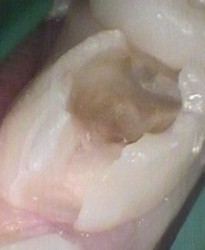

Massive decay hidden Large hidden decay exposed

Restored